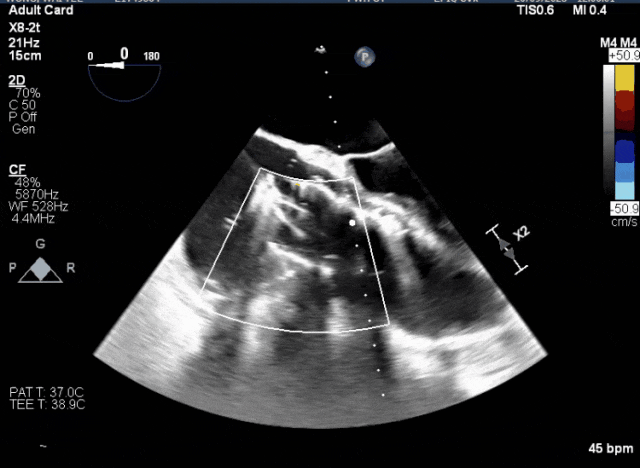

術中TEE觀察夾持件的位置

1、心率慢(<50bpm),術后起搏器植入風險,術前需評估心電圖情況;2、CT顯示主動脈瓣機械瓣置換術后,需明確三尖瓣是否同期做過修復。